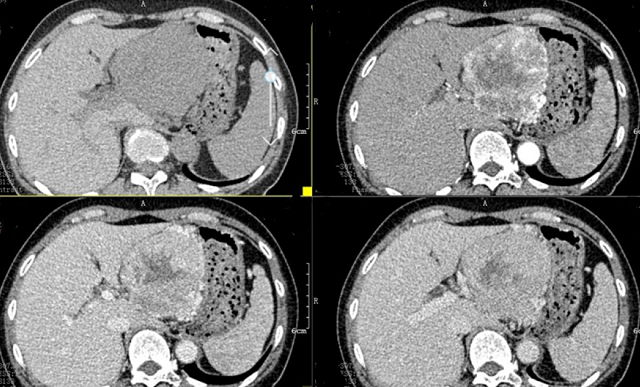

上腹部CT顯示胰腺巨大腫瘤

入院后,根據(jù)王女士病情,曹利平教授及其團(tuán)隊(duì)為她制定一套詳盡的術(shù)前檢查和治療方案。首先,安排做上腹部增強(qiáng)CT,并建議其先穿刺活檢明確病理。

“CT表現(xiàn)符合胰腺神經(jīng)內(nèi)分泌腫瘤,穿刺也證實(shí)無(wú)誤,但是瘤體實(shí)在太大,直徑約12cm左右,腹腔內(nèi)的門(mén)靜脈、腸系膜上靜脈、脾靜脈以及腹腔干這些重要血管統(tǒng)統(tǒng)包繞進(jìn)去了,且與周?chē)Y(jié)腸系膜也有累及!

曹利平教授帶著團(tuán)隊(duì)成員逐一分析,隱藏在瘤體附近的血管就像埋在炸彈旁的導(dǎo)火索,稍有不慎,便會(huì)引爆這顆瘤體炸彈,要想把腫瘤完整切除,更是難上加難。